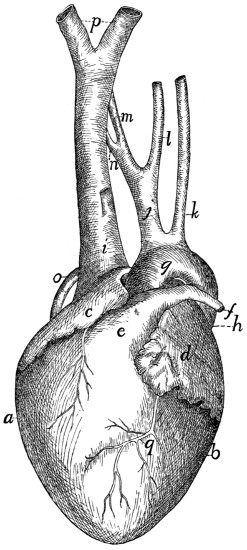

| 115. |

Heart |

276 |

| 116. |

Heart |

276 |

| 117. |

Inside of Heart |

278 |